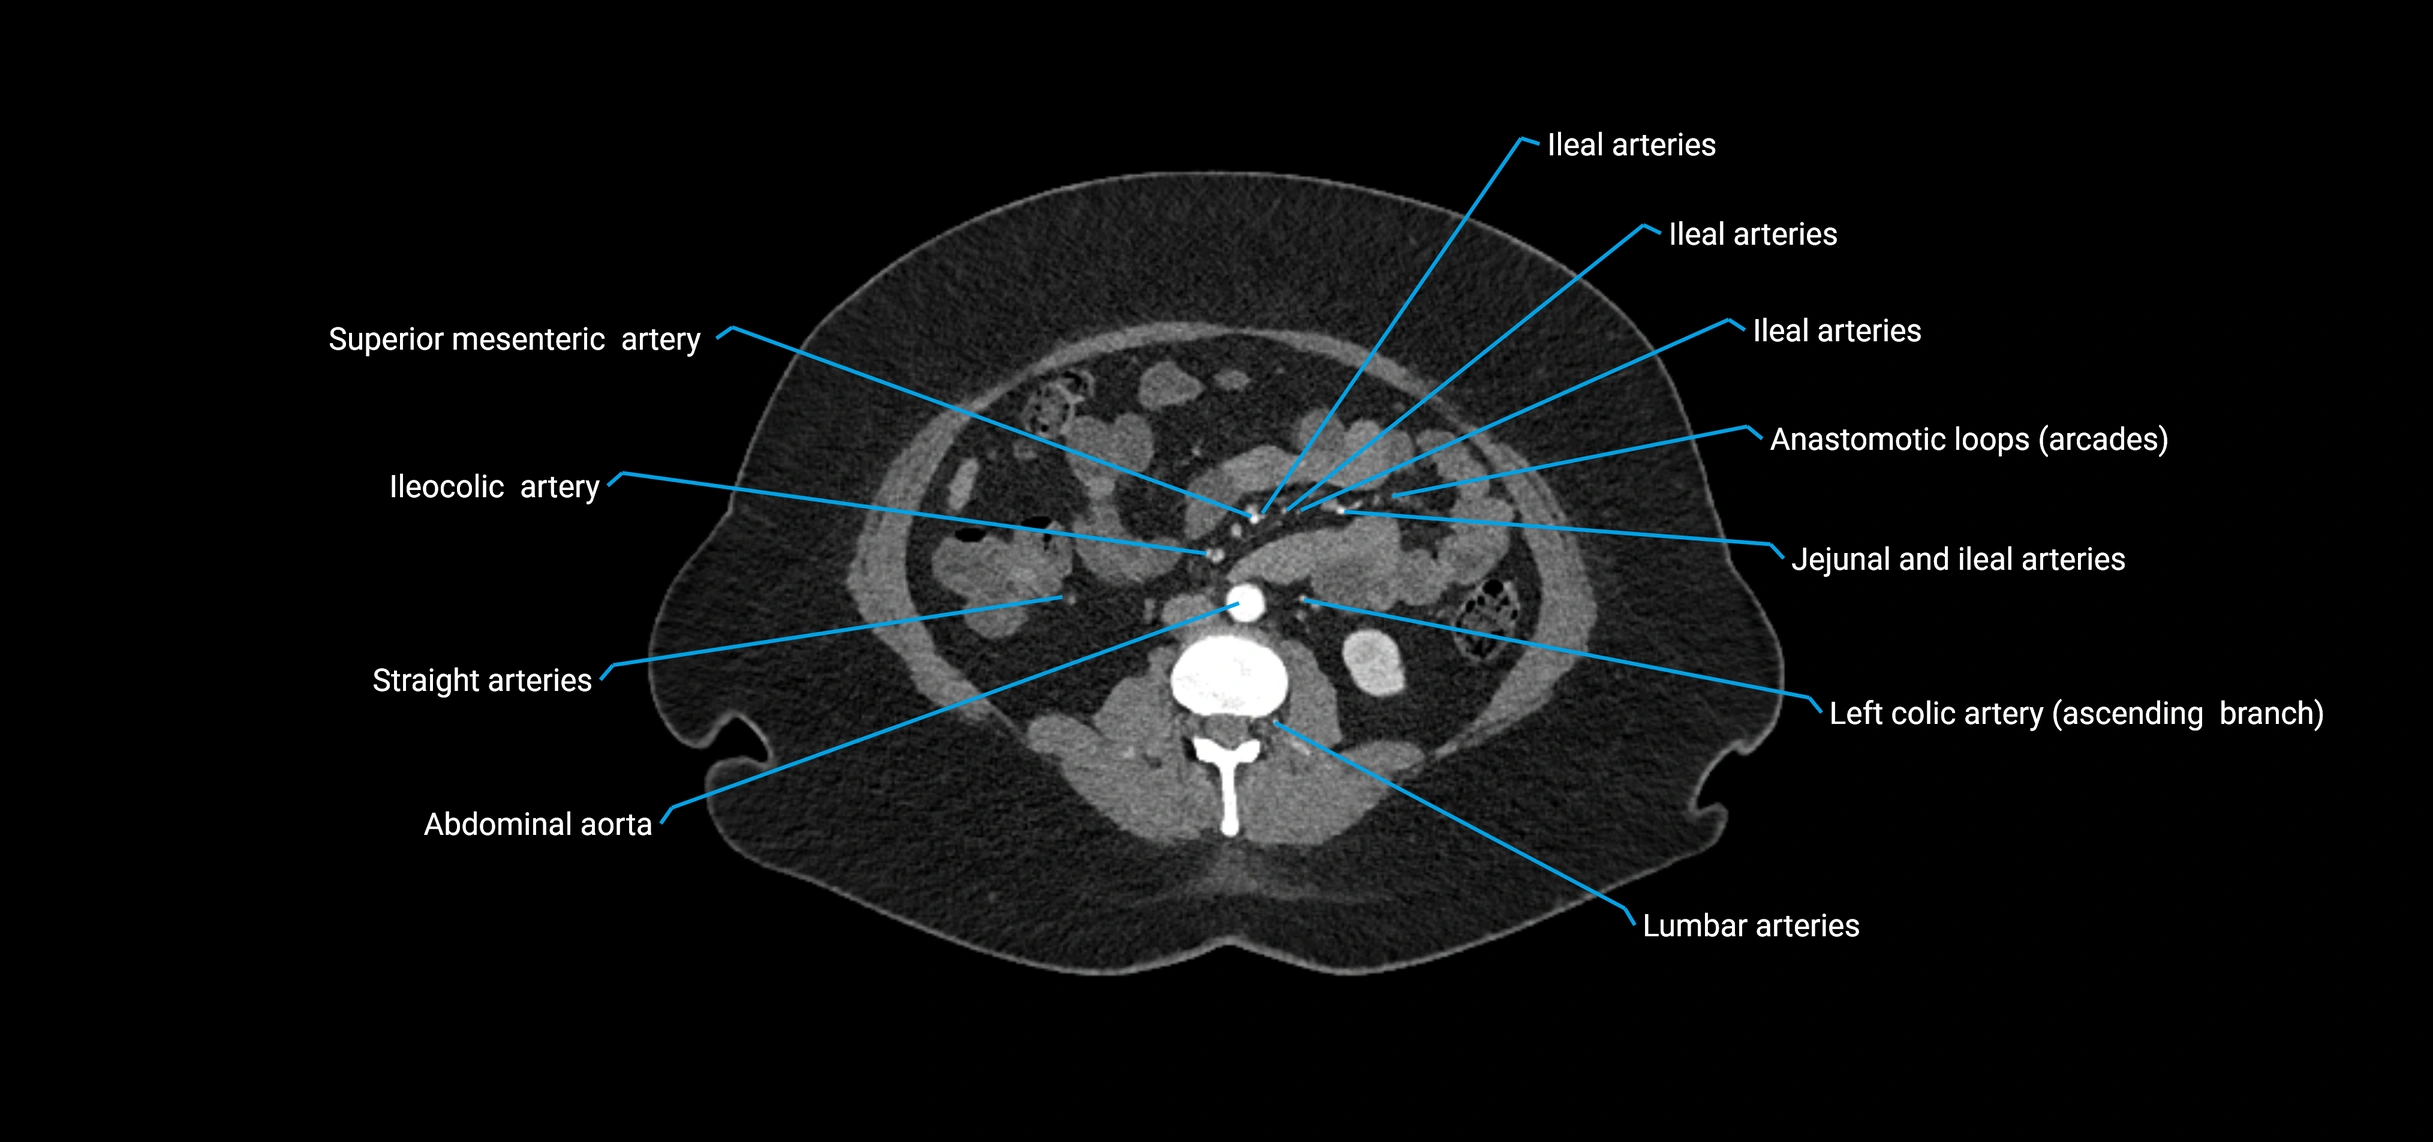

• Unpaired visceral branches: celiac trunk, superior mesenteric artery (SMA), inferior mesenteric artery (IMA)

Contrast-enhanced CT (CTA):

• Gold standard for abdominal aortic imaging

• Provides excellent detail of lumen, wall, aneurysm, thrombus, and branch vessels

• Multiplanar and 3D reconstructions help in aneurysm measurement, stent graft planning, and dissection evaluation

• Detects acute rupture, traumatic injury, or occlusion with high sensitivity